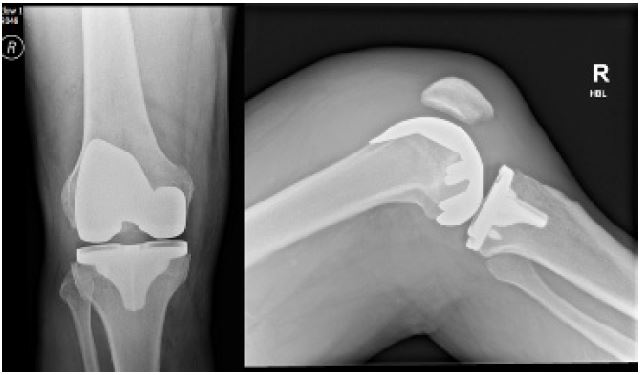

A 69-year-old male underwent right side robotic assisted total knee replacement for severe grade 4 knee osteoarthrosis in August 2023. His surgery was uneventful and he was discharged home with routine physiotherapy protocol and venous thromboprophylaxis. He was recovering well until 4 weeks after surgery when he presented in the emergency department with acute onset of pain and swelling of the right knee. He was able to weight bear and didn’t have any spike of fever. There wasn’t any history of bleeding disorder and he had already completed his 2 weeks of VTE prophylaxis medications. Clinical examination showed moderate to large diff use swelling around the knee, mildy raised temperature as compared to the other side, no significant erythema or redness. He had a range of motion of the knee from 10-90°. His blood tests for inflammatory markers showed C-Reactive Protein (CRP) 5 mg/dL and White Cell Count (WBC) of 6.8×109/ L. Radiographs of the right knee showed loss of supra and infra patellar fat pad suggestive of gross joint eff usion (Figures 1 & 2). His knee was aspirated with around 100 ml of dark colored frank blood which raised the suspicion of venous bleeding. The cultures were negative. He was sent home with advice of icing and elevation of knee at rest.

Figure 1, 2: Post-operative Anteroposterior and lateral radiographs of Knee showing total knee replacement in place and gross joint eff usion in form of loss supra and infra patellar fat pad.